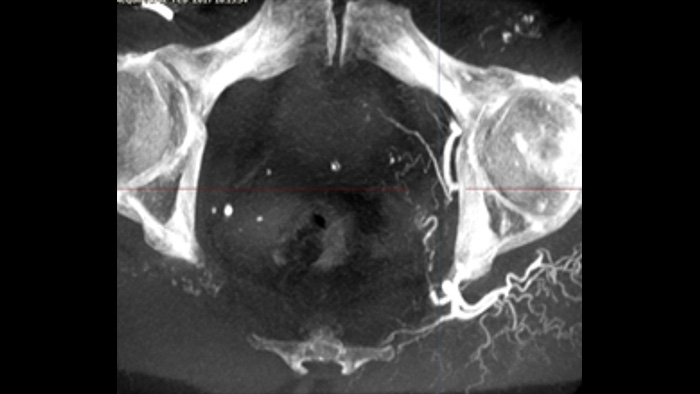

This X-ray acquisition technique generates a complete high-resolution 3D visualisation of cerebral, cardiac, abdominal or peripheral vasculature from a single rotational angiography run – all controlled via the touch screen at the table. This can improve visibility of tortuous or complex anatomy that may not be seen on a 2D or DSA image.

SmartCT Soft Tissue offers a cone-beam CT (CBCT) acquisition technique augmented with step-by-step guidance. Advanced 3D visualisation and measurement tools are all accessible on the touch screen module at table side. You are guided through key steps to support you in acquiring CBCT images first-time-right1 and to streamline your workflow.

SmartCT Vaso enables high-contrast and high-resolution imaging of cerebral vasculature based on a 3D rotational scan and an intra-arterial contrast injection. This technique enhances the visualisation of endovascular stents, flow diverters, or other devices, as well as vessel morphology down to the perforator level.